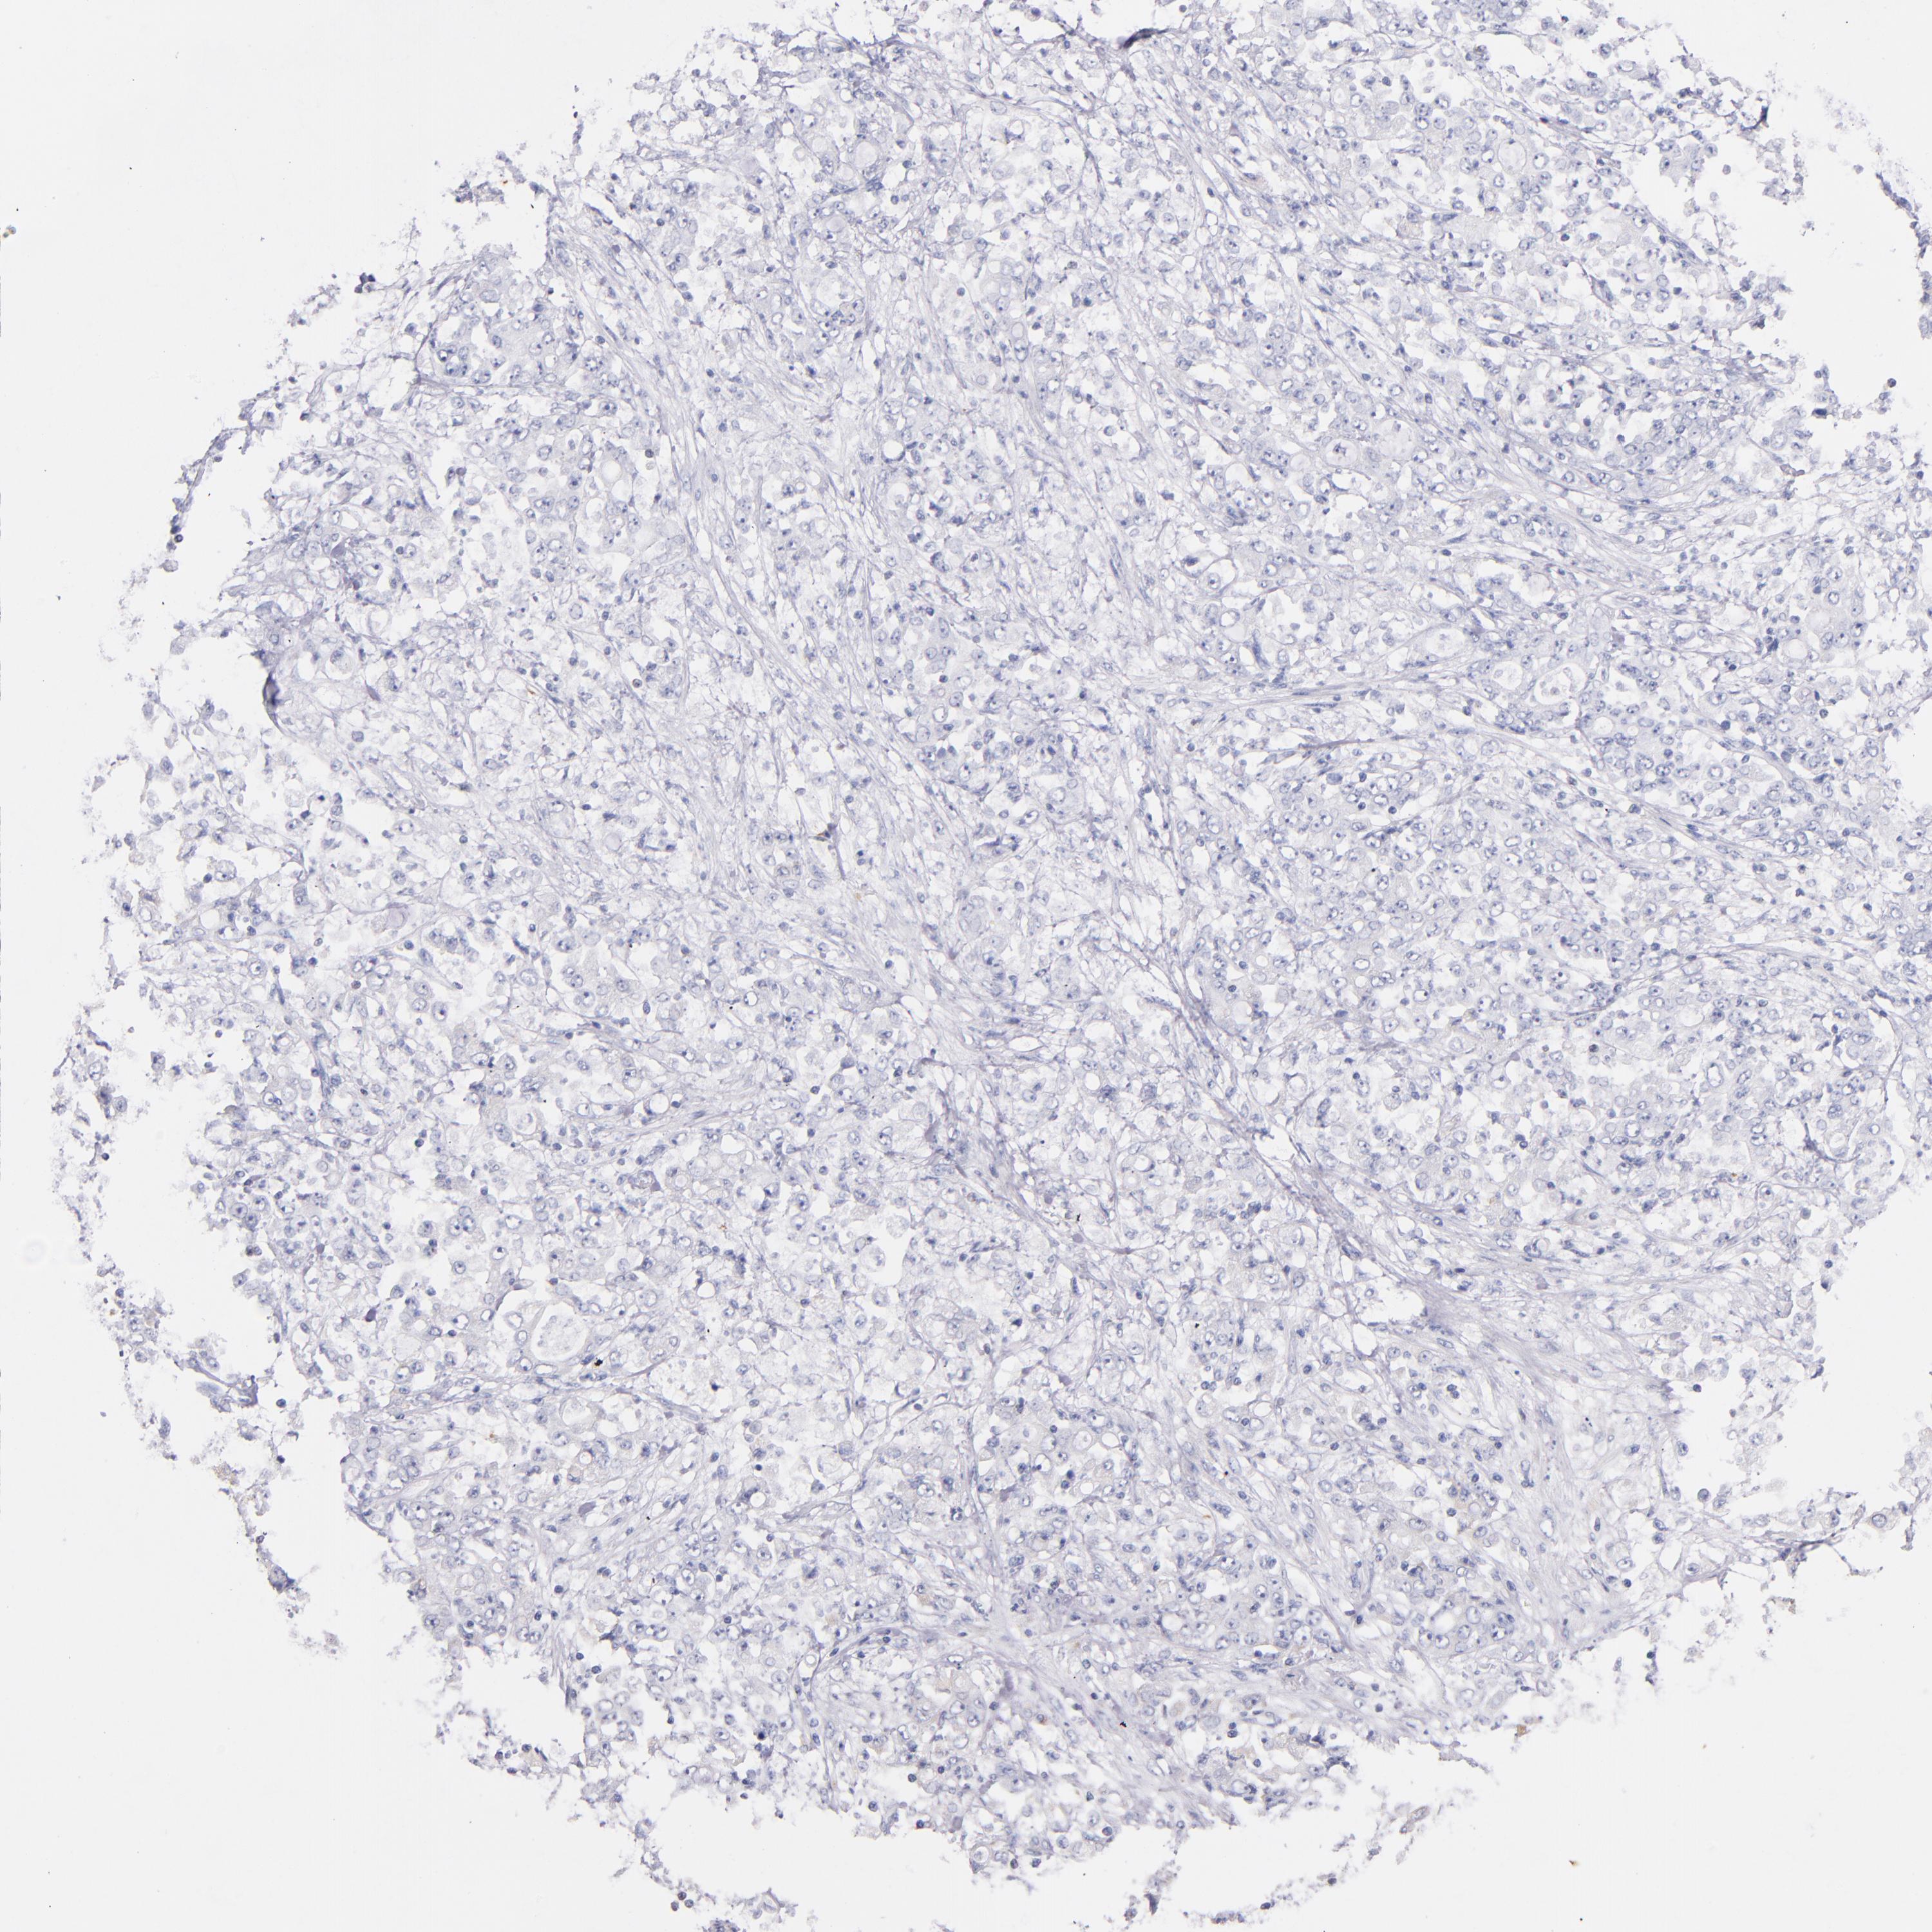

STOMACH CANCER - Protein expressioni

A mouse-over function shows sample information and annotation data. Click on an image to view it in a full screen mode. Samples can be filtered based on level of antibody staining by selecting one or several of the following categories: high, medium, low and not detected. The assay and annotation is described here.

Note that samples used for immunohistochemistry by the Human Protein Atlas do not correspond to samples in the TCGA dataset.

Antibody stainingi

Antibody staining in the annotated cell types in the current human tissue is reported as not detected, low, medium, or high, based on conventional immunohistochemistry profiling in selected tissues. This score is based on the combination of the staining intensity and fraction of stained cells.

Each image is clickable and will lead to virtual microscopy that enables deeper exploration of all samples and also displays staining intensity scores, fraction scores and subcellular localization as well as patient and tissue information for each sample.

Antibody HPA001819

Antibody CAB005416

Staining

High

Medium

Low

Not detected

Intensity

Strong

Moderate

Weak

Negative

Quantity

>75%

75%-25%

<25%

None

Location

Nuclear

Cytoplasmic/membranous

Cytoplasmic/membranous,nuclear

Adenocarcinoma, NOS

Adenocarcinoma, High grade